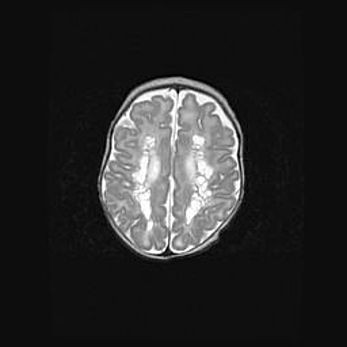

Сообщающаяся гидроцефалия. Кистозная энцефаломаляция головного мозга.

Возраст: 3 месяца 4 дня

Вес: 3100 г

Пол: женский

Окружность головы: 34 см

Срок гестации: 31 неделя

Кистозная энцефаломаляция головного мозга - одна из форм поражения головного мозга в детском возрасте. Характеризуется возникновением множественных и распространённых кист в коре, белом веществе и подкорковых образованиях головного мозга у плодов, новорождённых и детей раннего возраста. Развитие кистозной энцефаломаляции связано с внутриутробной асфиксией и гипотонией, родовой травмой, тромбозом синусов, пороками развития сосудов, инфекциями, сепсисом и другими причинами. Наиболее значимые инфекционные агенты: вирусы простого герпеса, цитомегалии, краснухи, токсоплазмы, энтеробактерии, золотистый стафилококк и другие.